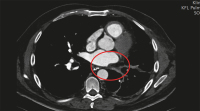

Pulmonalvenenstenose

Abbildung 5: Computertomographie: Pulmonalvenenstenose

Keywords:

Computertomographie

,

Pneumologie

PVS